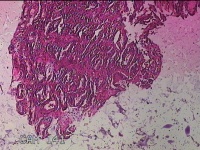

胃窦粘膜

性别

女

年龄

37岁

临床诊断

慢性胃炎

一般病史

阵发性胸痛3天。

标本名称

大体所见